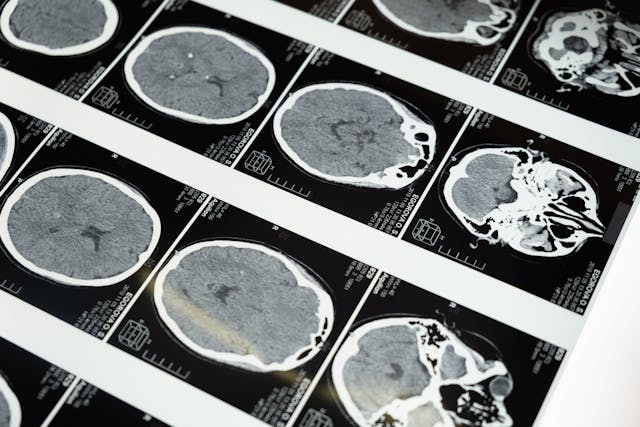

Angiografia głowy jako narzędzie diagnostyczne w neurologii

W przypadku występowania objawów neurologicznych, takich jak nagłe i intensywne bóle głowy, omdlenia, zaburzenia widzenia, niedowład kończyn czy zawroty głowy, lekarz może zlecić wykonanie angiografii głowy. Badanie to umożliwia dokładne odwzorowanie układu naczyniowego mózgowia, co pozwala na ocenę stanu tętnic i żył w obrębie czaszki. Dzięki niemu można wykryć niebezpieczne zmiany, takie jak tętniaki, przetoki tętniczo-żylne, zwężenia naczyń czy zakrzepy, które mogą prowadzić do poważnych powikłań neurologicznych, w tym udaru mózgu. W Rakoniewicach pacjenci mogą skorzystać z badania rezonansu magnetycznego głowy, które – uzupełnione o sekwencje angiograficzne – umożliwia kompleksową ocenę zarówno tkanek mózgowych, jak i naczyń. Dzięki nowoczesnemu oprogramowaniu oraz technikom kontrastowym uzyskane obrazy są wyjątkowo szczegółowe i mogą stanowić podstawę do postawienia precyzyjnej diagnozy. Co ważne, angiografia z użyciem rezonansu magnetycznego jest metodą bezpieczną nawet dla pacjentów z obciążeniami neurologicznymi, co czyni ją szczególnie przydatną w diagnostyce chorób ośrodkowego układu nerwowego.